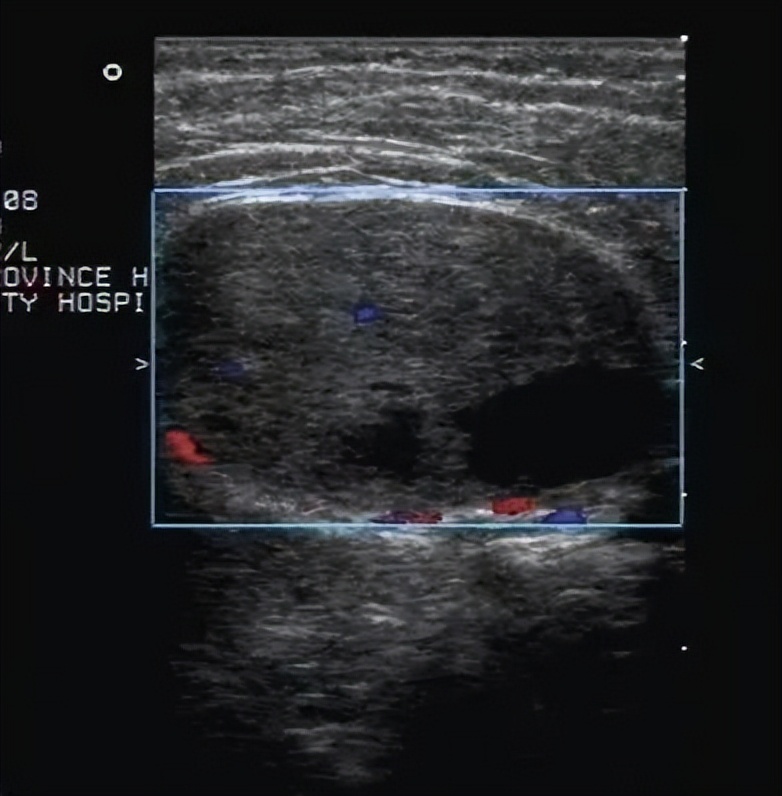

副乳癌